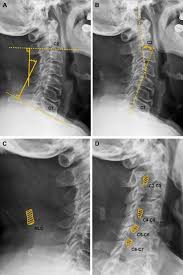

Ligamentum nuchae — das nackenband (ligamentum nuchae) ist ein paariges band aus elastischem bindegewebe, das als rückenseitige verspannung der halswirbelsäule dient. It covers the spines of c1 to c6 vertebrae. What does ligamentum nuchae mean? It runs from the external occipital protuberance along the tips of the spinous processes of the. Ligamentum nuchae — das nackenband (ligamentum nuchae) ist ein paariges band aus elastischem bindegewebe, das als rückenseitige verspannung der halswirbelsäule dient. The ligamentum nuchae is a large median ligament composed of tendons and fascia located between the posterior muscles of the neck. ( plural ligamenta nuchae ). It extends from the external occipital protuberance and median.

This ligament connects under the facet joints to create a small curtain over the posterior. The ligamentum nuchae are very strong. Looking for online definition of ligamentum nuchae in the medical dictionary? In chiari malformation treatment, decompression and duraplasty with a harvested ligamentum nuchae showed similar outcomes to pericranial and artificial grafts.3. The ligamentum nuchae is a large median ligament composed of tendons and fascia located between the posterior muscles of the neck. Medical definition of ligamentum nuchae: It extends from the external occipital protuberance and median. Continuous with the supraspinous ligament. What does ligamentum nuchae mean? A layer of tissue that protects the spinal cord. The ligamentum flavum forms a cover over the dura mater: A median ligament of the back of the neck that is rudimentary in man but highly developed and. It runs from the external occipital protuberance along the tips of the spinous processes of the.

Nuchal ligament creates the median fibrous septum in the middle of the muscles of the two parts of posterior neck. A layer of tissue that protects the spinal cord. What does ligamentum nuchae mean? The ligamentum nuchae is a large median ligament composed of tendons and fascia located between the posterior muscles of the neck. Continuous with the supraspinous ligament. It covers the spines of c1 to c6 vertebrae. A medium ligament of the back of the neck that is rudimentary in humans but highly developed and medical definition of ligamentum nuchae. Ligamentum nuchae — das nackenband (ligamentum nuchae) ist ein paariges band aus elastischem bindegewebe, das als rückenseitige verspannung der halswirbelsäule dient. It extends from the external occipital protuberance and median. This ligament connects under the facet joints to create a small curtain over the posterior. Medical definition of ligamentum nuchae: Ligamentum nuchae — das nackenband (ligamentum nuchae) ist ein paariges band aus elastischem bindegewebe, das als rückenseitige verspannung der halswirbelsäule dient. A dorsal raphe and a midline fascial septum.